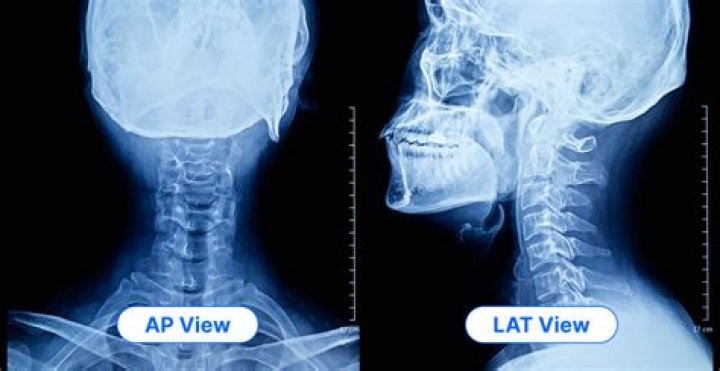

What is an AP medical test?

Reviewed on 3/29/2021. AP, X-ray: An X-ray picture in which the beams pass from front-to-back (anteroposterior). As opposed to a PA (posteroanterior) film in which the rays pass through the body from back-to-front.